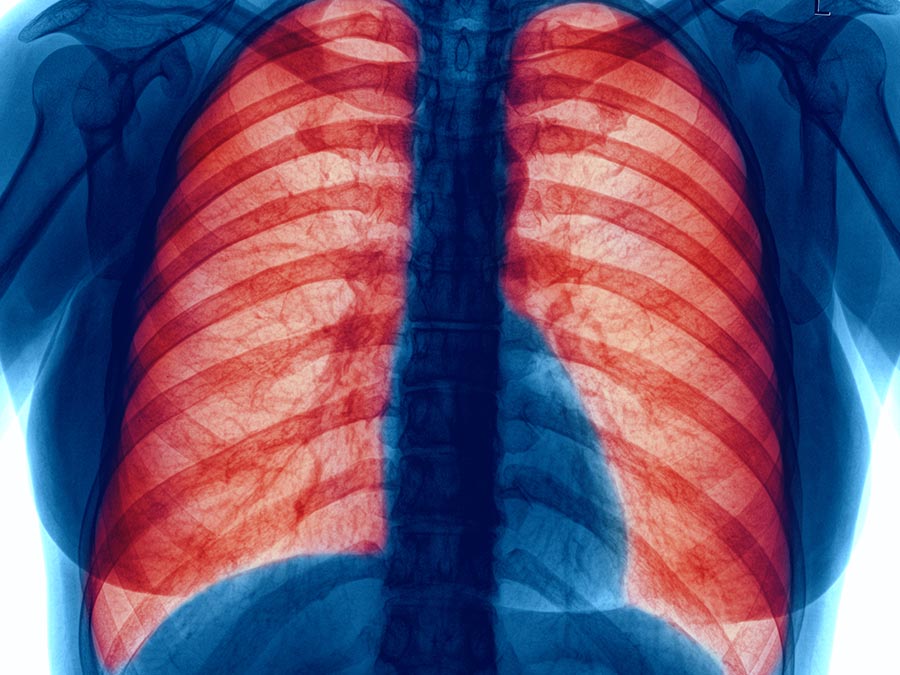

¿Qué es la Enfermedad Pulmonar Obstructiva Crónica?

La Enfermedad Pulmonar Obstructiva Crónica (EPOC) es un padecimiento que se caracteriza por la dificultad para respirar y que afecta al 10% de la población mexicana. Según la Organización Mundial de la Salud, la principal causa de la EPOC es la exposición al humo del tabaco (fumadores activos y pasivos).

“La EPOC es una enfermedad respiratoria ocasionada por exposición al humo, polvo, gases y, sobre todo, por el consumo de tabaco. Se presenta principalmente en personas mayores a 45 años y consiste en una obstrucción de los bronquios; es decir, se estrechan y no permiten el libre flujo de aire, lo que trae como consecuencia una malformación irreparable”, comenta el Dr. Macías.